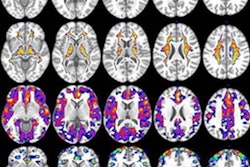

Three-dimensional overlay shows the regional pattern of statistically significant correlation between QSM and tau-PET values, including the inferior temporal gyrus. Images courtesy of Brain.Interestingly, the difference between the two groups in QSM and tau-PET results was even more pronounced in beta-amyloid-positive individuals ages 65 and younger. In addition, both a voxel-wise analysis and region-of-interest-based analysis confirmed the associations between QSM and tau-PET with the "stereotypical spread of Alzheimer's disease," the authors added.